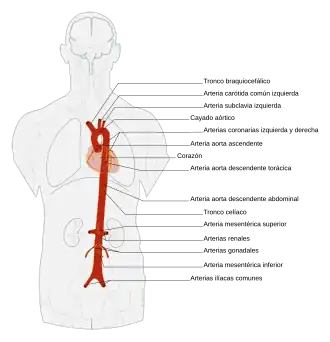

La aorta es la principal arteria del cuerpo humano,[1] midiendo hasta 2,5 cm de diámetro (a la altura del diafragma) en adultos.[2] Se origina en el ventrículo izquierdo del corazón, su trayecto inicial es ascendente, posteriormente forma un arco llamado arco aórtico y desciende atravesando el tórax hasta llegar al abdomen, donde se divide en las 2 ilíacas comunes que se dirigen a los miembros inferiores.[3] Transporta y distribuye sangre rica en oxígeno y da origen a todas las arterias del sistema circulatorio excepto las arterias pulmonares que nacen en el ventrículo derecho del corazón.[4]

La aorta se divide en tres partes: aorta ascendente, arco aórtico o cayado aórtico y aorta descendente. Esta última se divide en dos partes separadas por el diafragma que se llaman aorta torácica y aorta abdominal.

Es la sección que va desde el arco aórtico hasta el lugar donde se divide en las arterias ilíacas comunes. En su camino atraviesa el diafragma que la diferencia en dos regiones: aorta torácica y aorta abdominal.

La aorta y sus ramas

La aorta ascendente emite dos ramas, las arterias coronarias, que distribuyen sangre en el miocardio. Luego, gira hacia el lado izquierdo del cuerpo, donde forma el cayado de la aorta (arco aórtico), el cual desciende y termina a nivel del disco intervertebral que separa la cuarta y la quinta vértebra dorsal.

Al continuar su descenso se convierte en aorta descendente, se aproxima a los cuerpos vertebrales, cruza el diafragma, atraviesa el abdomen, y se divide, a la altura de la cuarta vértebra lumbar en las arterias ilíacas primitivas, que llevan sangre a los miembros inferiores. A lo largo de su recorrido emite vasos que se ramifican en otros más pequeños que distribuyen la sangre en los distintos órganos. En estos, las arterias se dividen en arteriolas, y después en capilares, que irrigan todos los tejidos del cuerpo, excepto los alveolos pulmonares.

- Ramas de la porción ascendente: arterias coronarias.

- Ramas del cayado de la aorta (arco aórtico): tronco braquiocefálico, arteria carótida común izquierda y arteria subclavia izquierda.

- Ramas de la porción descendente.

- Ramas de la porción descendente torácica: arterias bronquiales, arterias esofágicas, ramas mediastínicas de la aorta torácica y arterias intercostales posteriores.

- Ramas de la porción descendente abdominal:

- Ramas parietales: arteria diafragmática inferior y arterias lumbares;

- Ramas viscerales: tronco celíaco, arteria mesentérica superior, arteria suprarrenal media, arteria renal, arterias gonadales (arteria ovárica/arteria testicular), y arteria mesentérica inferior.

- Ramas terminales: arteria sacra media, arterias ilíacas primitivas derecha e izquierda.[12]